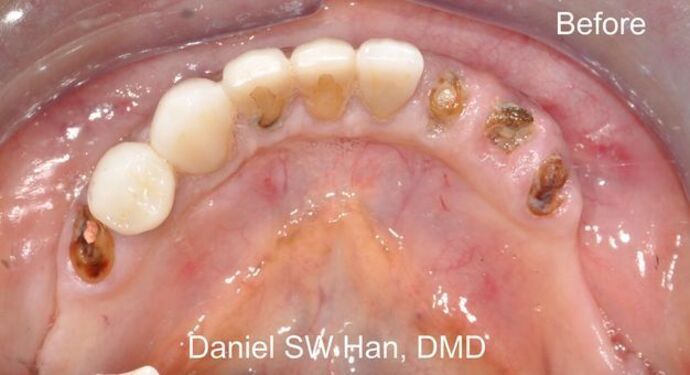

Full Mouth Reconstruction: Case 3: Teeth in One Day

Mandibular full mouth reconstruction was done in one day (Teeth in One day). The patient has had asymmetric bite and smile. This caused bite collapse and TMJ issues for many years. The patient was treated with several dental implants to reconstruct the mandibular teeth back in one day. This 'Teeth in One Day' procedure is possible for almost every patient; however, the case must be carefully selected and prepared prior to the actual treatment day.